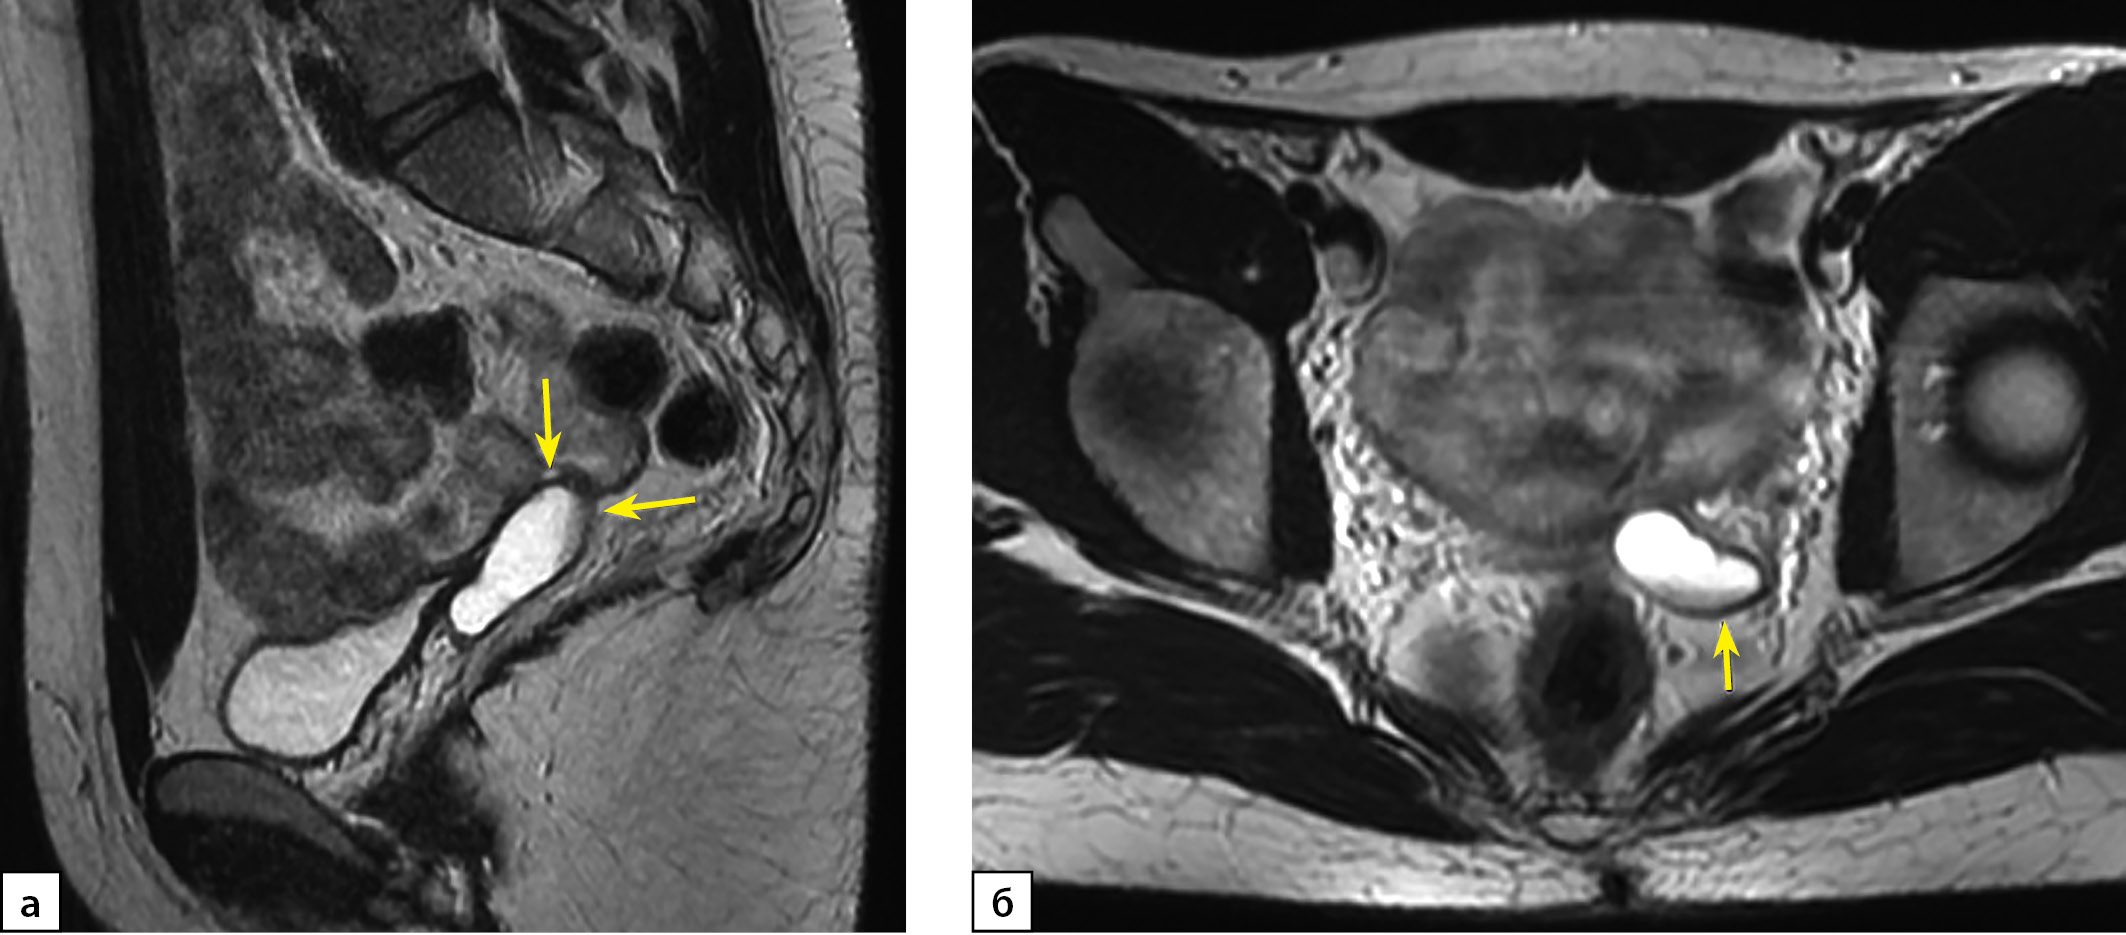

Рисунок 2 а, б. МРТ органов малого таза пациентки Х, Т2-ВИ, корональная плоскость.

Примечание: Гонады в паховых областях (стрелки).

Правое яичко (рис. 2а) расположено в области наружного пахового кольца, имеет правильную овальную форму, четкие контуры, размеры 3,8х2,5х2,1 см (объем 10,37 см3), структура яичка однородная. Придаток яичка не определяется.

Левое яичко (рис. 2б) расположено в области внутреннего пахового кольца, имеет правильную овальную форму, четкие контуры, размеры 2,6х2,1х3,3 см (объем 9,36 см3), структура яичка однородная. Придаток яичка не определяется.

Figure 2 a,b. MRI of the patient X pelvis, T2-WI, coronal plane.

Note: Gonads in the groin (arrows).

The right testicle (Fig. 2a) of an oval shape, legible contours, 3.8x2.5x2.1 cm of size (volume 10.37 cm3), with homogeneous structure is located in the external inguinal ring area. The epididymis is not defined.

The left testicle (Fig. 2b) of an oval shape, legible contours, 2.6x2.1x3.3 cm of size (volume 9.36 cm3), with homogeneous structure is located in the internal inguinal ring area. The epididymis is not defined.